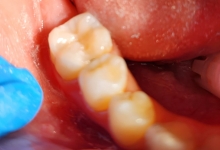

Boala parodontala are un caracter progresiv. Pentru cazurile mai grave, recomandam tratamentul parodontal chirurgical rezectiv sau regenerativ.

Recomandam controale periodice (3-6 luni) pentru igienizari profesionale: detartraj, periaj dentar, air-flow etc. Aceste operatiuni asigura sanatatea gingiei, iar osul alveolar si ligamentele parodontale isi pastreaza integritatea.